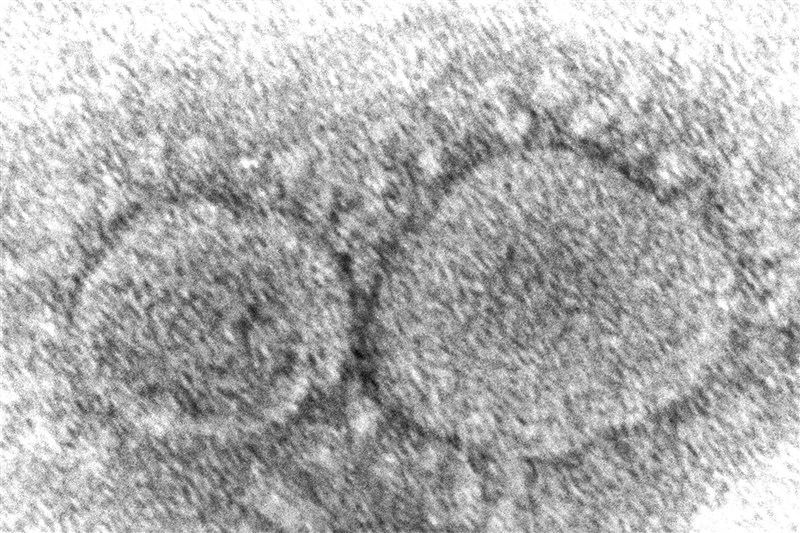

英國通報新冠新變異株 首例BA.2.86 |2023.08.19 語音朗讀 1103觀看次 字級 大 中 小 圖為電子顯微鏡下的新冠病毒。圖/美聯社 【本報綜合外電報導】英國衛生安全局(UK Health Security Agency,UKHSA)18日指出,已在國內檢測出新冠病毒變異株BA.2.86首例,這名患者近期並未有旅遊史。路透報導,美國疾病管制暨預防中心(U.S. Centers for Disease Control and Prevention,CDC)18日指出,正在追蹤一種新冠病毒高度突變新型變異株BA.2.86。BA.2.86變異株已在以色列、丹麥和美國被檢測發現。 前一篇文章 颶風希拉里襲洛杉磯 加州84年首個熱帶風暴登陸 下一篇文章 美日韓領袖峰會 重申台海和平重要性 熱門新聞 01【分數之外】看見另一種英文2026.04.0802男子氣概照護員 日本長照新力量2026.04.0503【徵稿】2026.04.0304【無所不知】 北庭故城遺址(上)2026.04.0305【轉移注意力】往理想中的自己邁進2026.04.0506降雨兩樣情 南部水庫沒解渴2026.04.0607美課藥品重稅 台灣沒優惠 2026.04.0408租賃車業者違法攬客 觀光署:最高罰200萬元2026.04.0709一紙學歷換錢景 美學位價值遭質疑2026.04.0510【青春部落】 那一次,我應該這樣說2026.04.03 訂閱電子報 台北市 天氣預報 台灣一週天氣預報 相關報導 北韓又射飛彈 拒絕南韓示好葛里爾:中美關係穩定 盼設貿委會寧夏梨花盛開打破集體領導 越南總書記兼國家主席阿提米絲2號飛越月球背面 破紀錄江蘇夢幻櫻花河